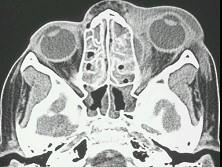

眼眶蜂窝织炎(如图)的严重并发症有 ( )A、败血症B、眼球萎缩C、视神经萎缩D、化脓性脑膜炎E、海绵窦血栓形成

问题 眼眶蜂窝织炎(如图)的严重并发症有 ( )

选项 A、败血症 B、眼球萎缩 C、视神经萎缩 D、化脓性脑膜炎 E、海绵窦血栓形成

答案 ACDE